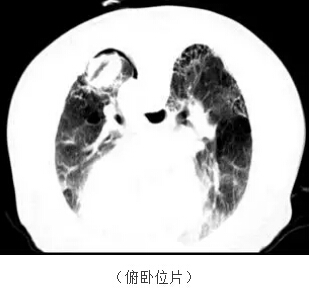

第二位患者已經(jīng)80多歲了,一直有慢性的肺心病,體檢發(fā)現(xiàn)了肺上一個(gè)3cm左右的腫塊,得知有局部消融這種微小創(chuàng)傷的治療手段,仿佛發(fā)現(xiàn)了救命稻草。

從上圖看患者肺部有嚴(yán)重的肺纖維化、肺大泡,肺功能很不好,左下肺還有一個(gè)3cm左右的腫塊

上圖:我們同樣在CT的引導(dǎo)下把消融針穿入腫瘤內(nèi)部,并獲取了部分腫瘤組織標(biāo)本用于病理定性檢查。

上圖:消融結(jié)束即刻掃描可見(jiàn)沒(méi)有氣胸等損傷。術(shù)后1月增強(qiáng)CT掃描,看到病灶完全沒(méi)有強(qiáng)化。第三位患者因肺癌接受過(guò)分子靶向治療,但一段時(shí)間以后病灶開始有反彈趨勢(shì),他聽病友介紹來(lái)門診咨詢并選擇了微波消融這種治療方法。